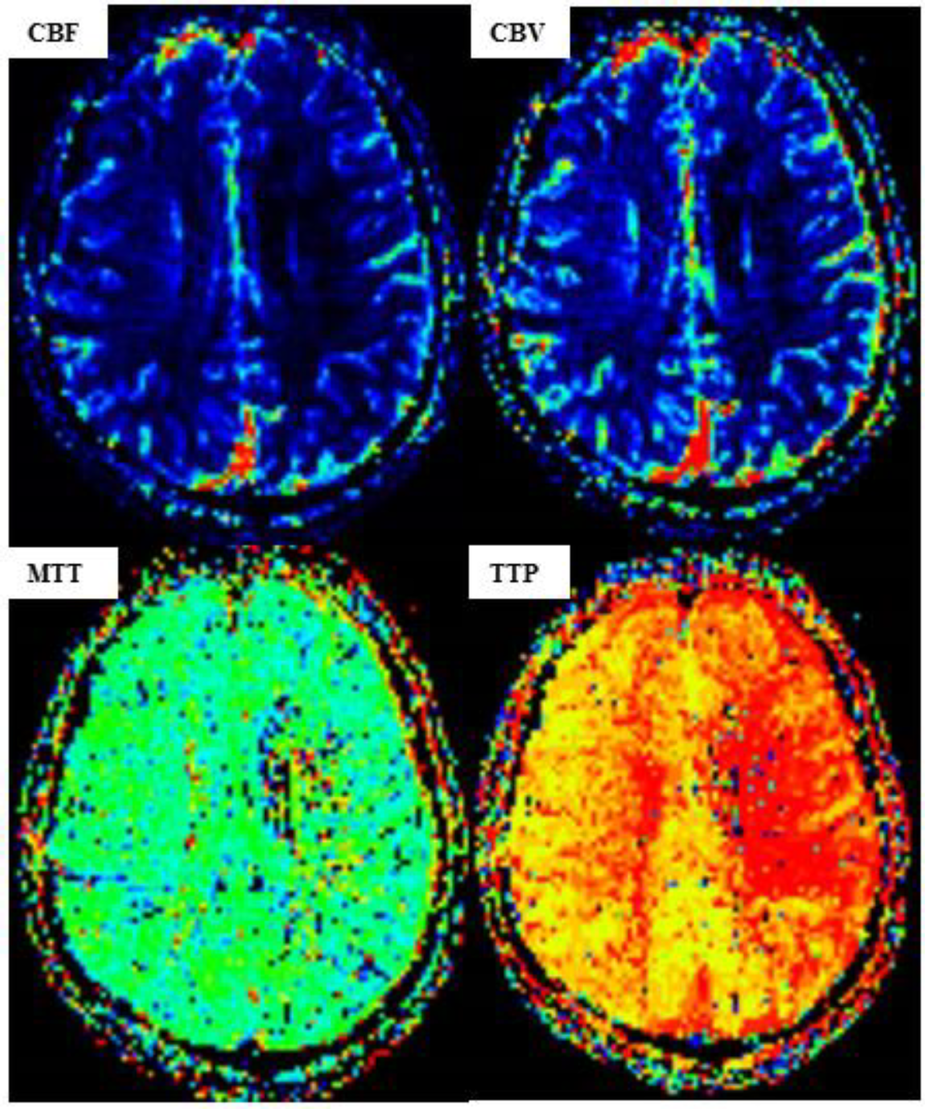

Figure 5

MR perfusion-weighted imaging (PWI) after carotid artery stent implantation (CAS). [PWI showing a lower cerebral blood volume (CBV) and cerebral blood flow (CBF) in the left hemisphere than those in the right hemisphere, while the time to peak (TTP) and mean transit time (MTT) are significantly higher.]

The high-risk factors of CHS include long-term hypertension, carotid stenosis of the treatment side > 90%, and occlusion or stenosis of the contralateral carotid artery > 80%. Some studies indicate that for high-risk patients, it is recommended to control blood pressure < 120/80 mmHg after CAS. On the 10th day of admission, we performed stent implantation of the C1 segment of the right internal carotid artery and left subclavian artery for the patient. ASA 100 mg, plavix 75 mg, and nifedipine controlled-release tablets of 30 mg were given on the day of the operation. The embolic protective device used during the operation was SpiderFX 6.0 mm (EV3) protective umbrella. Transient vagal reaction occurred during stent implantation and balloon dilation, the heart rate and blood pressure decreased, and 0.5 mg of atropine was immediately injected intravenously, following which the patient's heart rate and blood pressure returned to normal, and ECG and blood pressure monitoring were done in real time. Heparin (800 IU ivgtt) was used three times after the operation. Low-molecular-weight heparin (5000 IU ih q12h) was used for 3 days after the femoral artery sheath was removed. Collateral circulation improved after the operation. Then, the patient was transferred to the NICU, and the systolic blood pressure was controlled at a range of 100 and 110 mmHg. Several hours later, the patient developed motor aphasia, and the muscle strength of the right limb was grade 3. A bedside TCD examination and brain CT examination were performed immediately. TCD showed that the flow velocity of the middle cerebral artery had changed little before and after the operation (Figure 3). The brain CT showed no hemorrhage and obvious swelling of the cortex, and CHS was preliminarily excluded (Figure 4A). On the second day, MRI cerebral perfusion was done, which revealed a decrease in perfusion in the left frontotemporal lobe which was more severe than that before surgery (Figure 5). It was considered that the patient’s condition may be aggravated by hypoperfusion cerebral infarction due to the strict control of blood pressure after the operation. He was immediately treated with blood volume supplementation and pressure boosting. During this process, it was found that the weakness of the right limb was aggravated when the blood pressure was decreased (the systolic pressure was lower than 120 mmHg), and the weakness of the right limb was relieved when the blood pressure was increased (the systolic pressure was greater than 150 mmHg). On the third day after the operation, the patient regained his consciousness, but suffered from aphemia, and the muscle strength of the right limb was grade 0. Upon a reexamination of the brain CT, it could be seen that there was an enlargement of the low-density focus beside the left lateral ventricle (Figure 4B). After providing active medical treatment and rehabilitation physiotherapy, the patient was discharged from the hospital on the 10th day after the operation. At the time of discharge, he was conscious, but continued to have aphemia, and the muscle strength of the right limb was grade 3. A timeline with relevant blood pressure data is shown in Figure 6.